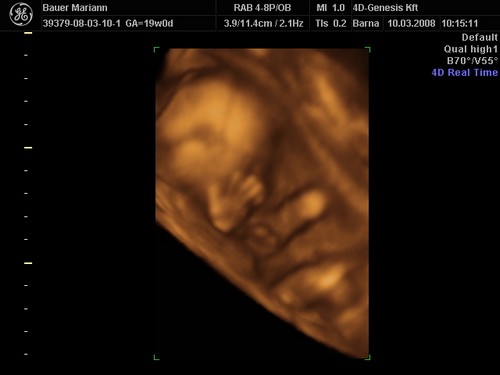

lányok tegnap bevettem egy maltofer vasat és olyan hasmenésem volt most reggel hogy hajjaj ez normális :?: na meg két pici tűszúrásnyi piros pötty lett a pocakomon,jujj megyek mert 10re oda kelll érni a genesisbe látjuk a kicsiket :D jajjj de jó

Drága picikéim nem voltak túl szereplős hangulatukba úgy kellett kikönyörögni őket a méhlepényből,és még igy sem letek túl élesek a képek.jázmin 266gr ,amy 300gr,jázmin egyszer úgy fejberúgta amyt úgy sajnáltam :D olyan édes formás kiscsajok el vagyok ájulva ,szép egézségesek tele pocakkal,megzabálom őket :D

De nekem eltalálták a 4DGenesisben, nálam tényleg 2 kukis van, igaz, én 2 héttel idősebb terhes voltam, mint te az első 4D-s kukucson.